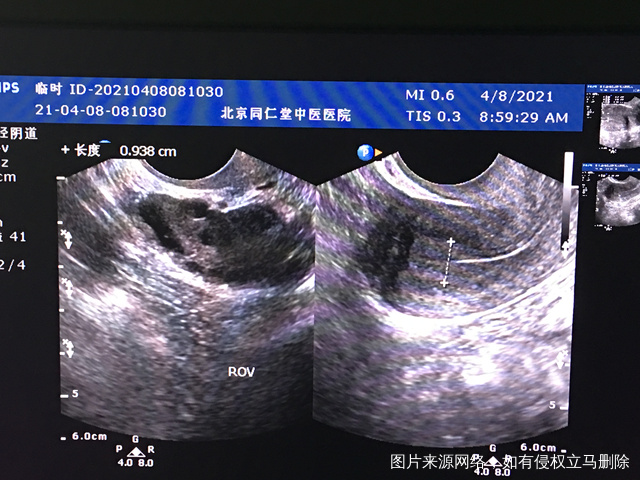

您好我月经不规律上次月经3月2日请问我现在这